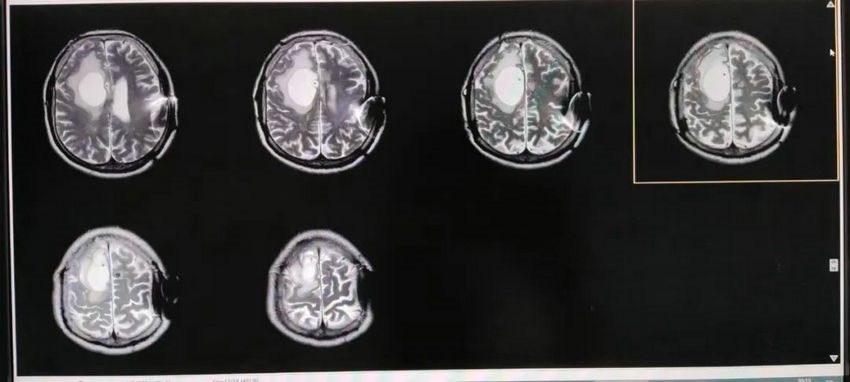

▲ 磁共振T2像显示左侧侧脑室旁囊肿,囊肿与侧脑室之间有分隔,对周围脑组织挤压形成囊周水肿;侧脑室前后角变得圆钝,三脑室扩张,此为脑积水的典型表现。